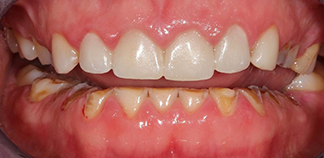

До лечения

Жалоба на стираемость зубов.

Как лечили

Проведено тотальное протезирование зубов коронками и винирами E-max.